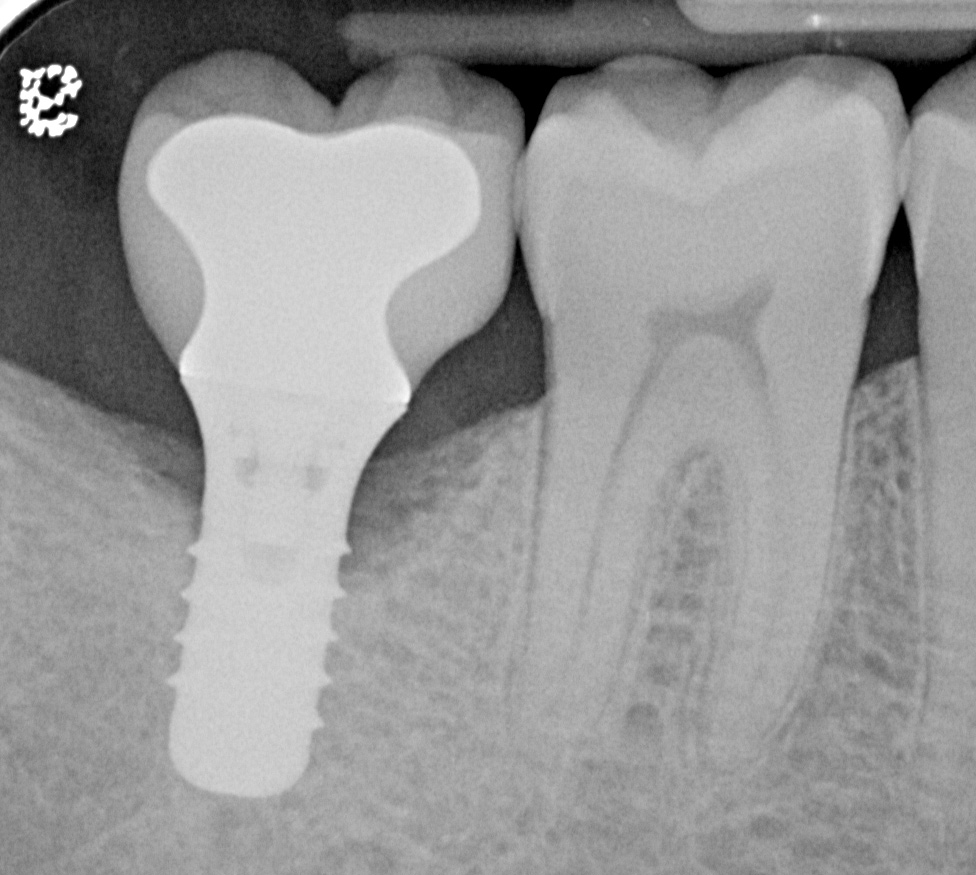

Fig 8. Radiograph taken 3 years after restoration of this mandibular right second molar implant demonstrating a peri-implant lesion.

Figure 8